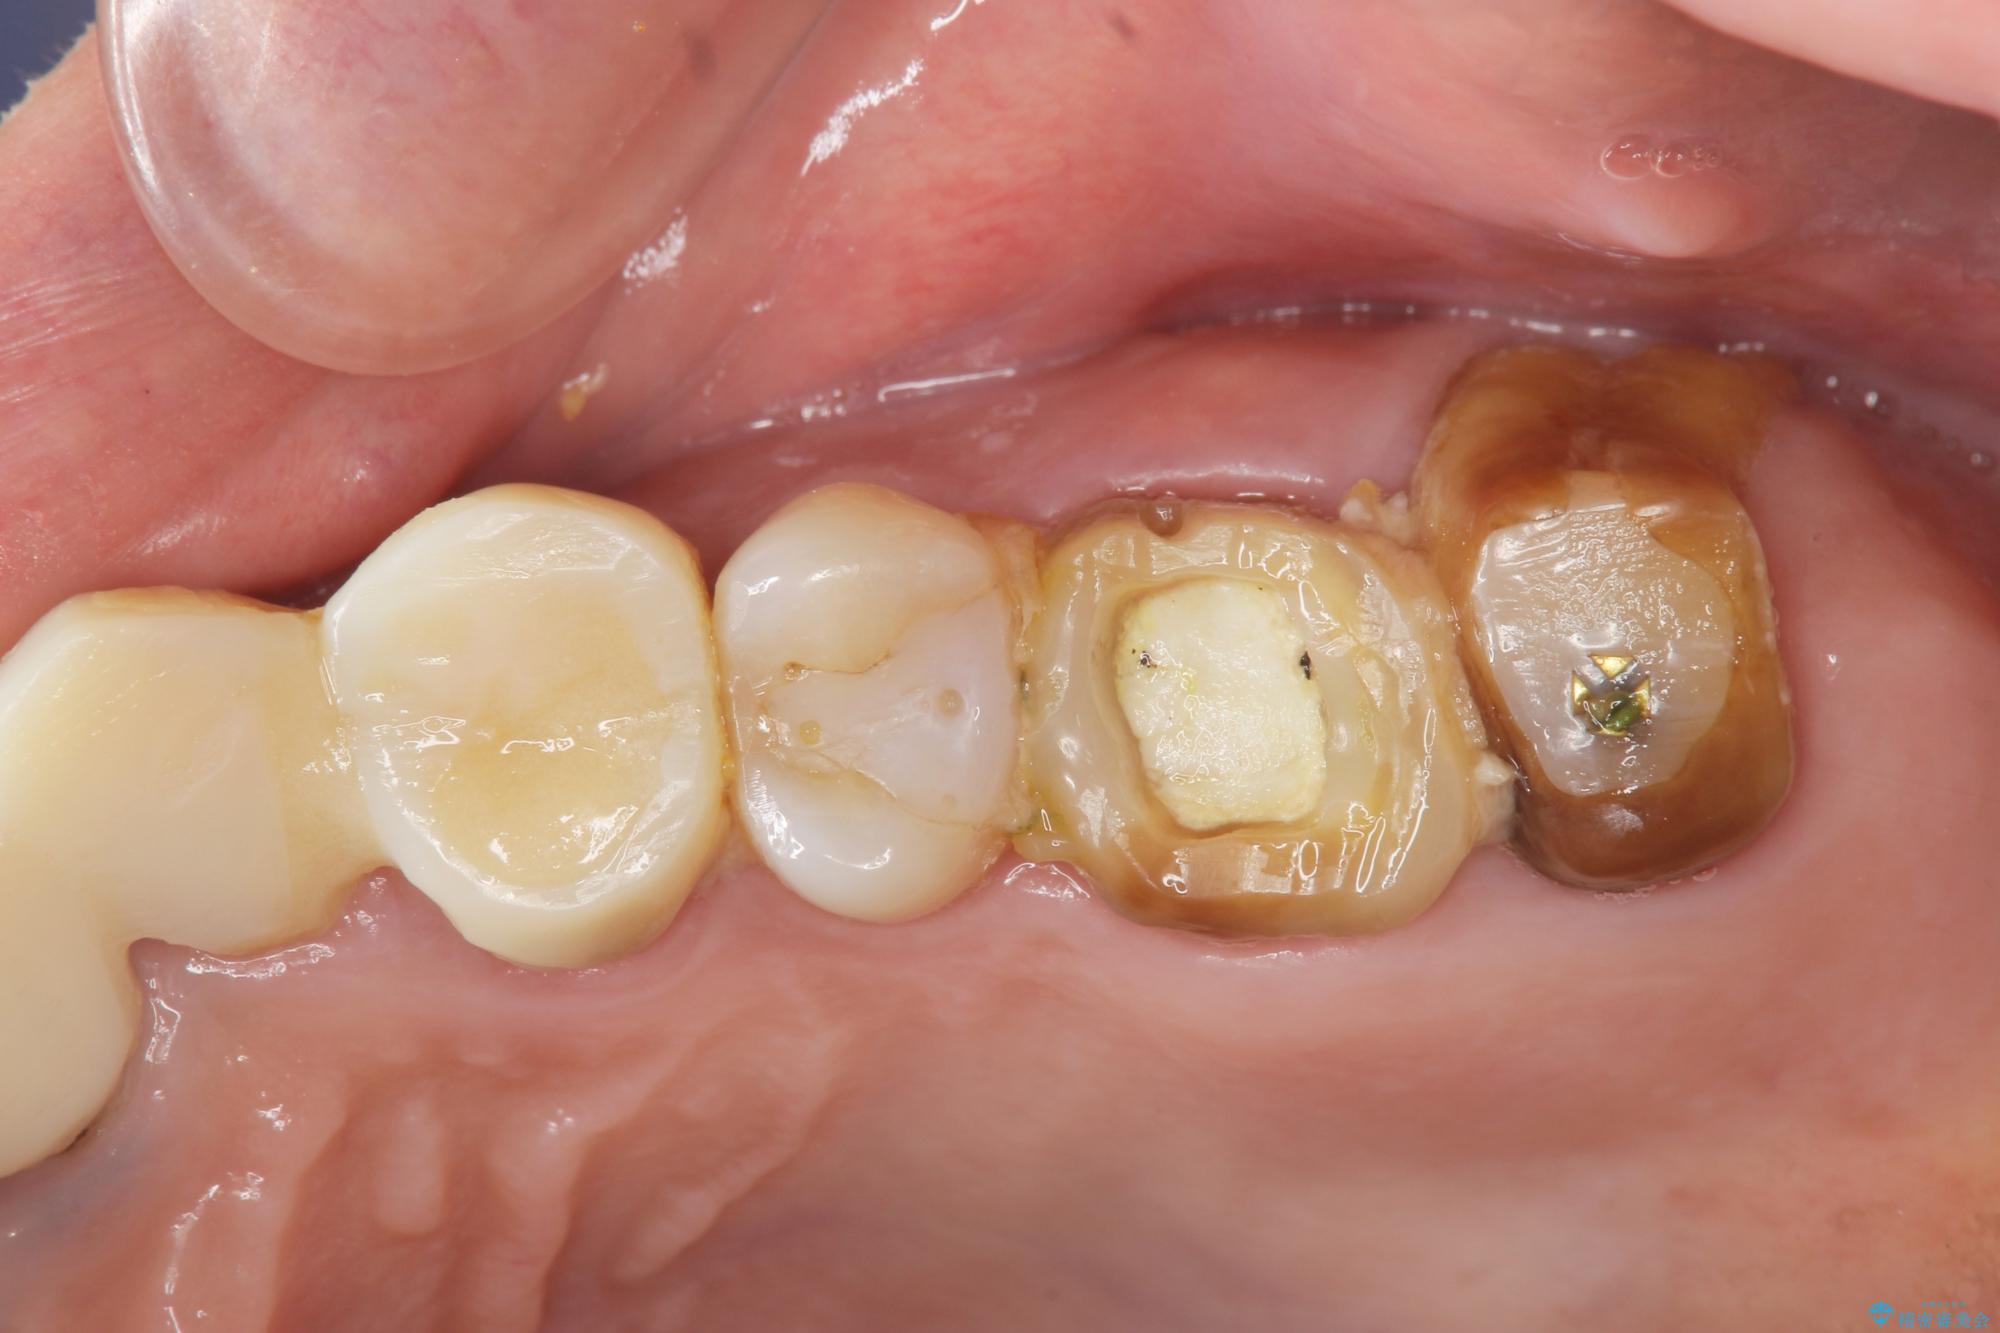

クラウンが装着されておらず、つぎはぎだらけの処置歯を、精度の高いセラミッククラウンを用いて歯ブラシのしやすい環境整備を行っていきます。

セラミッククラウンの治療は、天然の歯のような審美性を回復できることも大切ですが、精度が高くきっちりと歯ブラシを行いやすい状態を整えることで虫歯や歯周病の再発リスクを下げることも非常に大切です。